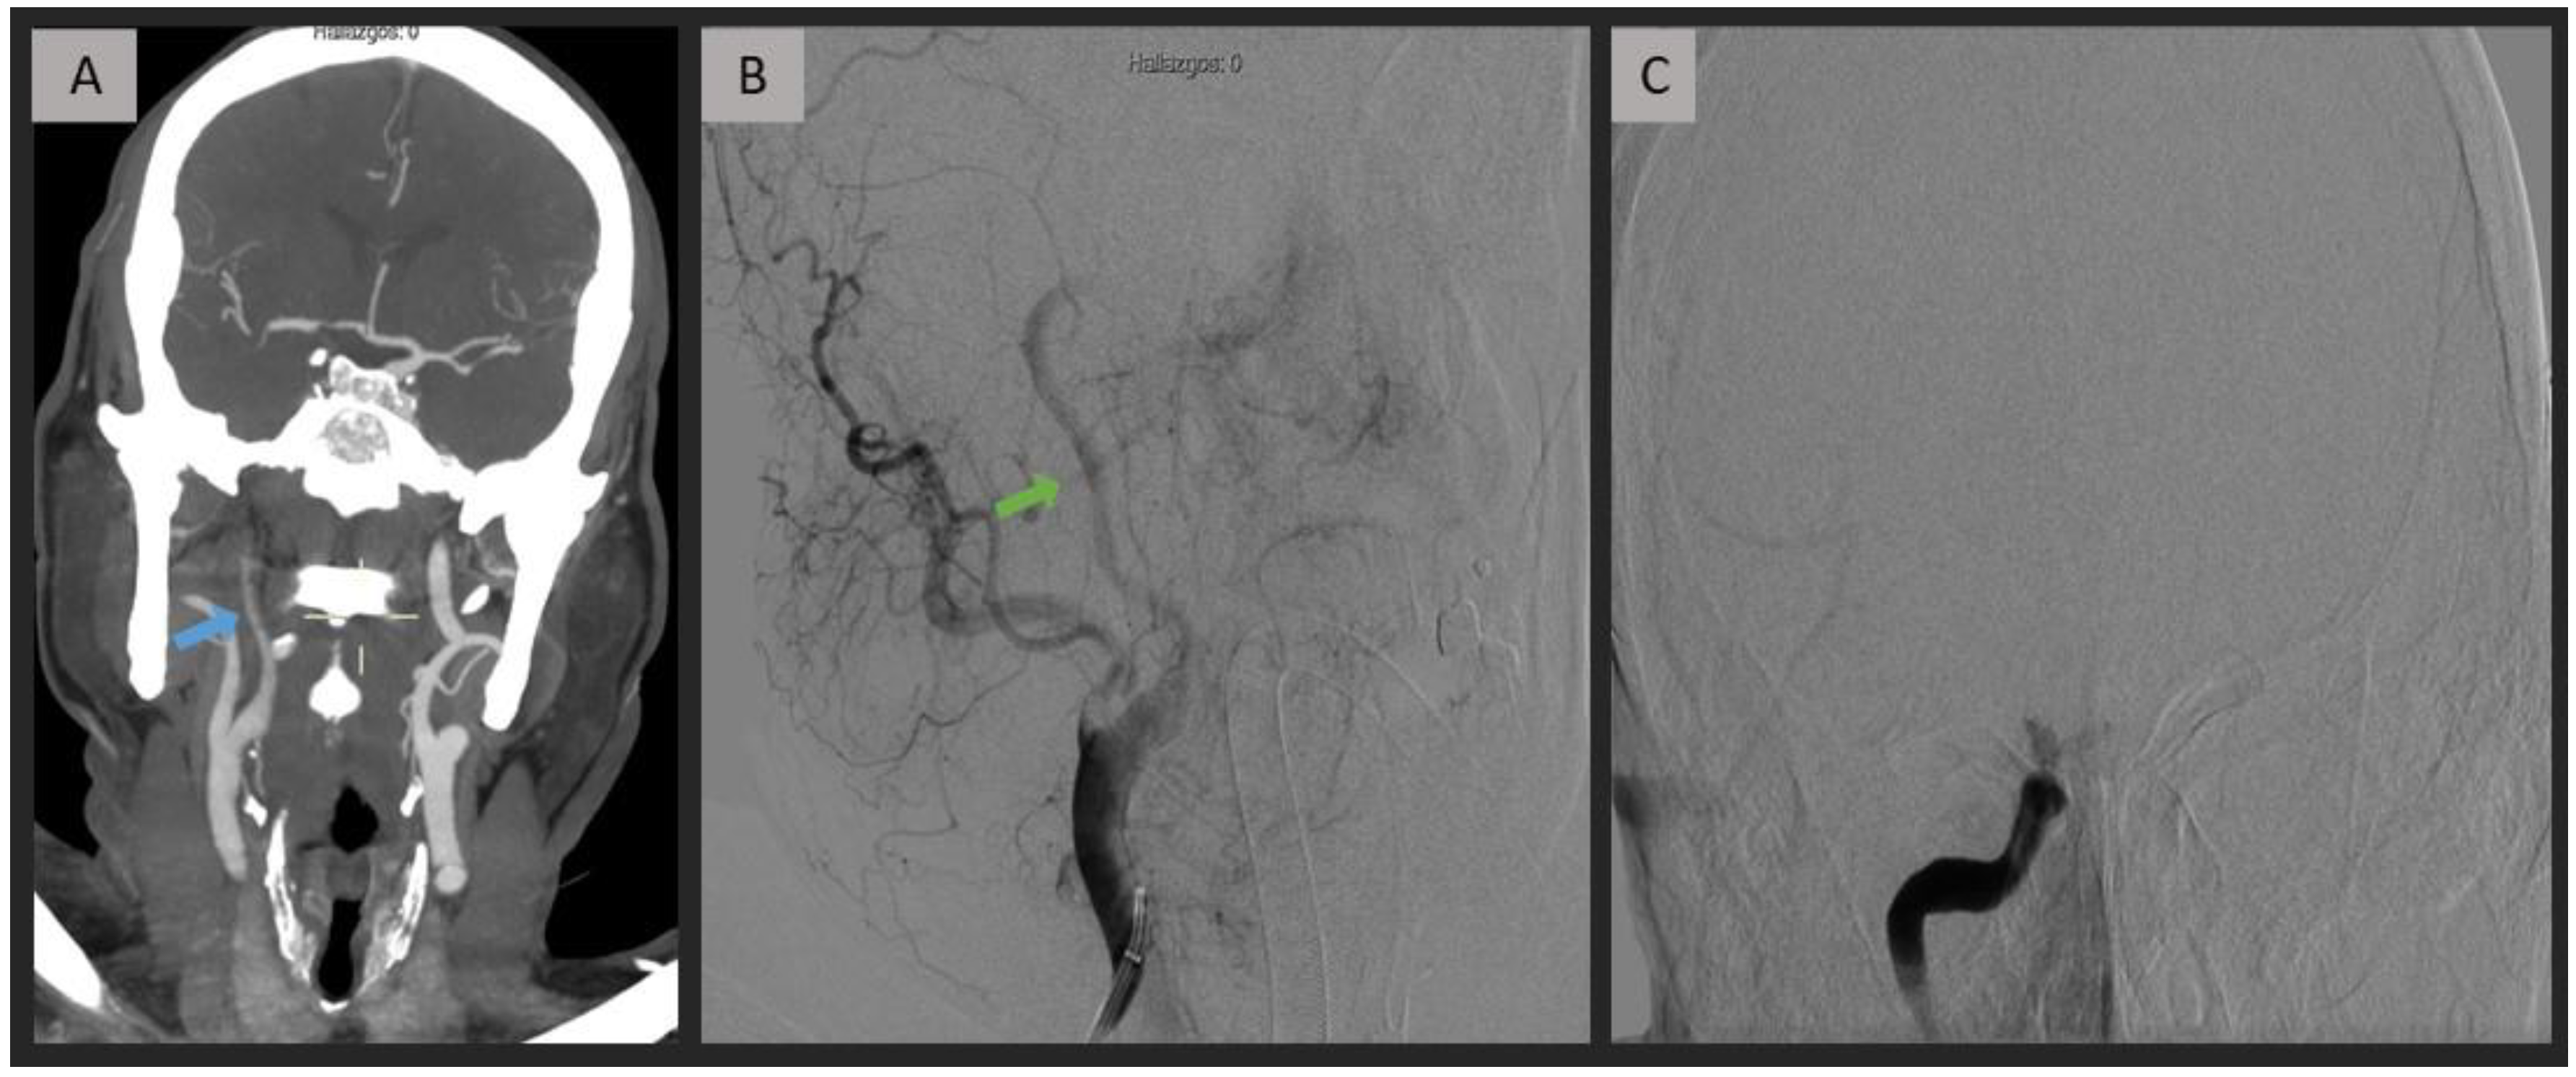

Figure 2.

Acute intracranial ICA occlusion caused by thromboembolism. CTA (A) demonstrates a progressive contrast decay in the extracranial region, extending towards the distal right ICA (blue arrow), while maintaining patency of the terminal bifurcation. DSA images (B,C) confirm an isolated intracranial occlusion while indicating the patency of the extracranial segment (green arrow). ICA = internal carotid artery; CTA = computed tomography angiography; DSA = digital subtraction angiography.